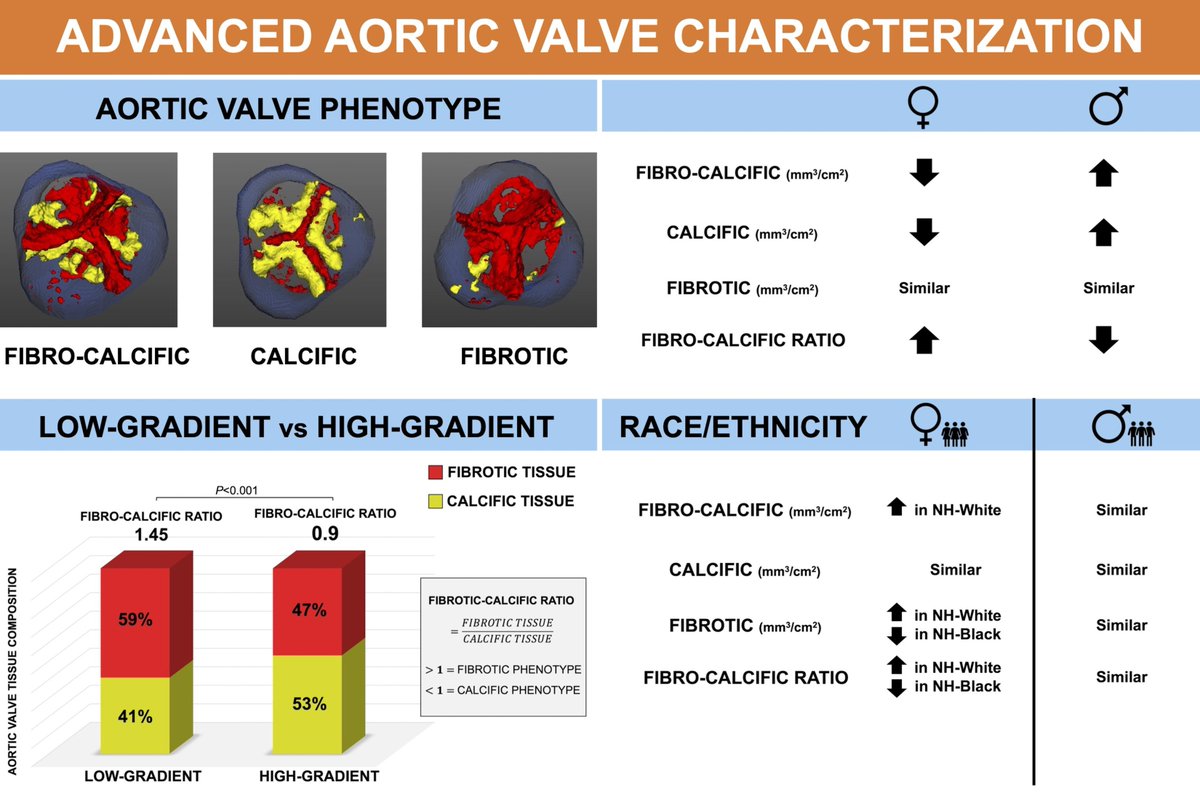

2/ Leandro Slipczuk Pamela Piña S. Aldo L Schenone, MD Carlos Gongora, MD FACC Andrea Scotti Edwin Ho Azeem Latib #AHAJournals Kaz Negishi@Cardiologist/ Heart Mafia ahajournals.org/doi/10.1161/CI…

📣 Check out our latest work on Advanced CT Aortic Valve Characterization just published on CircImaging A wonderful collaboration with Daniel Lorenzatti, MD. and our 💫 Team! Leandro Slipczuk 🔗 ahajournals.org/doi/10.1161/CI… Montefiore Heart Montefiore Health System